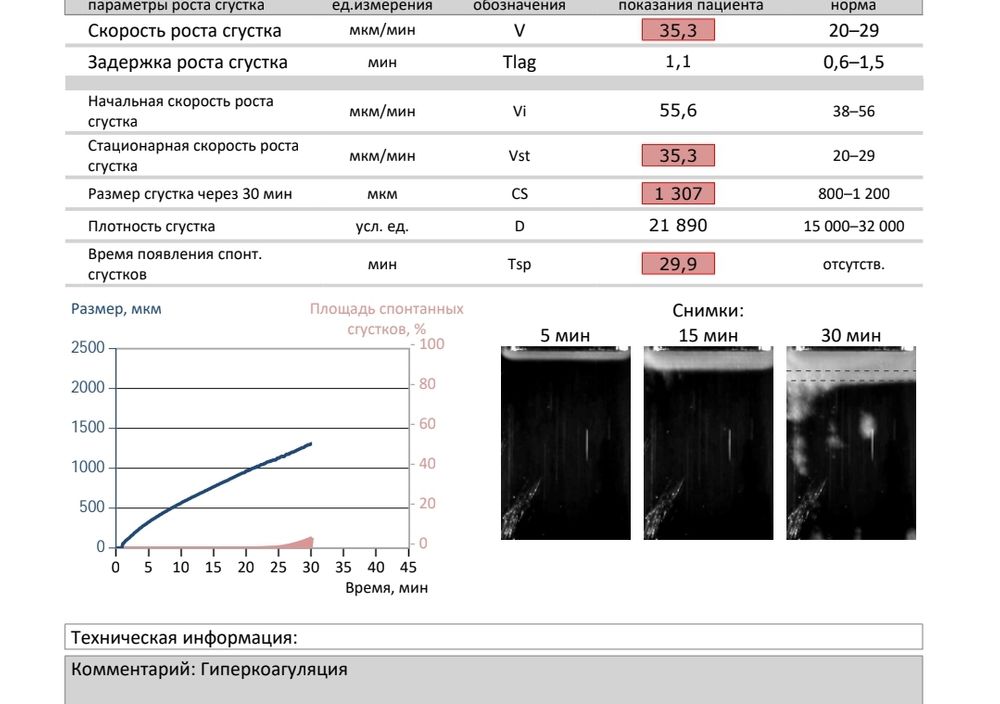

Криоперенос и тромбодинамика

Изображение

Добрый день. Девочки, подскажите, пожалуйста, кто нибудь заходил в крио перенос эмбриона при гиперкоагуляции? Стоит ли идти. Всегда был нормальный анализ, а сей